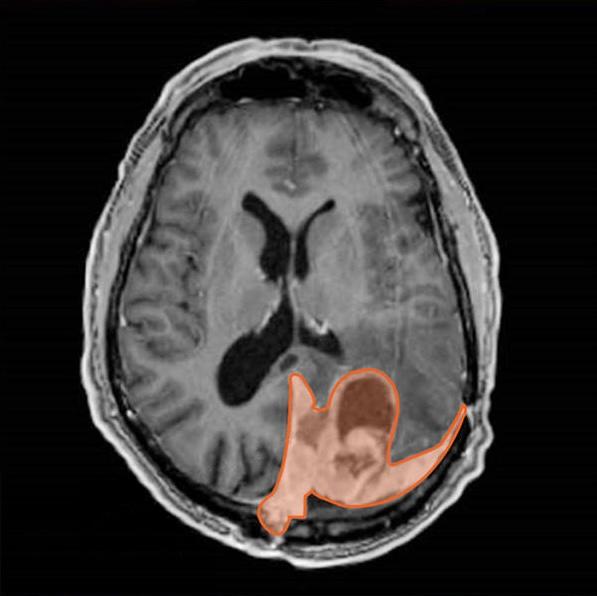

Resonancia magnética de encéfalo en la que se marca un meningioma en color naranja.

Imagen de una resonancia de una persona con un meningioma (en color naranja). Los investigadores crearon una firma de expresión genética que ayudaría a decidir el tratamiento para las personas con este tipo de cáncer de encéfalo.

Fuente: Instituto Nacional del Cáncer/NCI-CONNECT